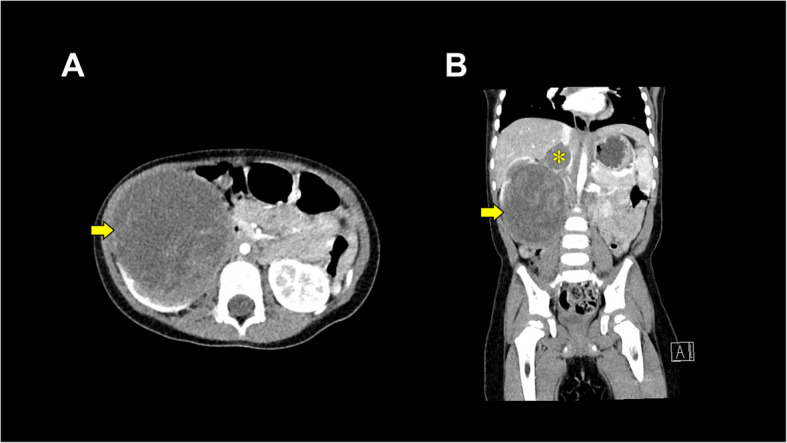

Case presentation: A 2-year-old boy with an IVC-extending Wilms tumor underwent nephrectomy. Anticipating hemorrhage, we employed an SL One® rapid infusion device via a Broviac™ central venous catheter. During a sudden, high-volume bleeding, transfusion was initiated at 23 mL/min and intermittently increased to 150 mL/min while preload was evaluated using transesophageal echocardiography, rapidly stabilizing hemodynamics. No rapid-transfusion-related complications, such as hyperkalemia or hypothermia, were observed, and the postoperative course was uneventful.